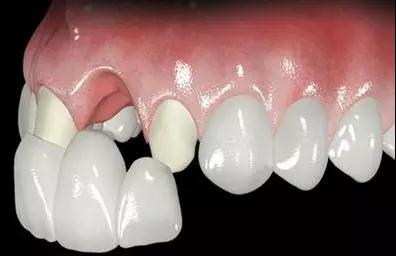

2~3个月后可镶固定义齿

(图为固定假牙)